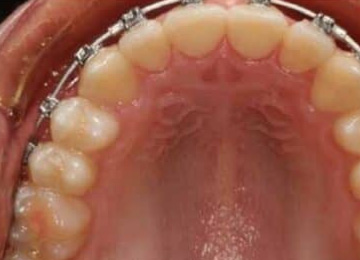

Одним из эффективных методов исправления прикуса у подростков после прорезывания зубов являются брекет-системы. Одним из препятствий к лечению во многих случаях становятся переживания подростков по поводу своего внешнего вида. В стоматологии "Интердентос" мы используем различные виды брекет-систем, в том числе и лингвальные, которые крепятся с внутренней стороны зубов.

Закреплением результата после снятия брекет-систем, как правило является использование ретенционного аппарата в виде пластинок или капп, а также в виде маленькой металлической дуги, закрепляемой с внутренней стороны зубов. Важно понимать, что чем раньше начато лечение по исправлению прикуса, тем быстрее оно проходит, с меньшими сложностями и более предсказуемым результатом. Кстати, оплата распределяется частями, по каждому этапу, так что не стоит пугаться, когда полная стоимость исправления прикуса выглядит внушительно.